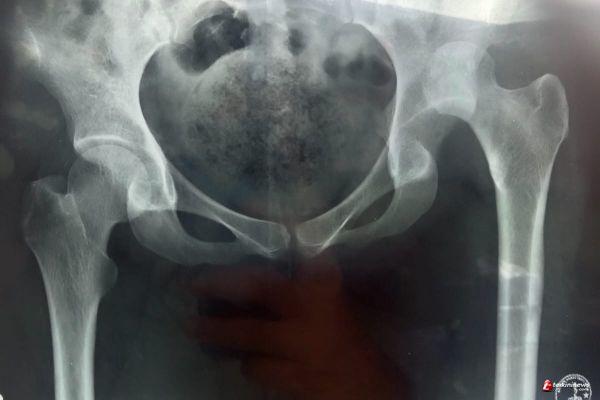

Korban tertindih karung padat berisi dos besar dan berat hingga mengalami patah tulang dan penyebab korban saat ini lumpuh tidak dapat beraktivitas sebagaimana mestinya.